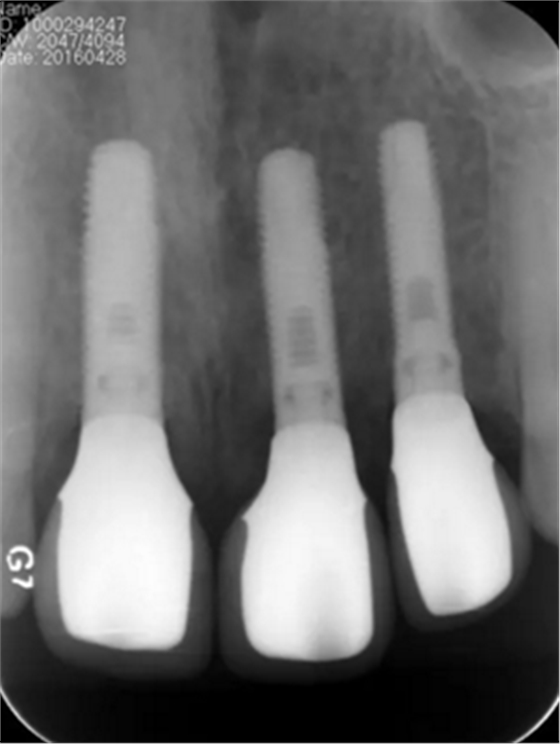

图13 术后即刻根尖片

图24 最终修复后即刻根尖片

(2)即刻种植、即刻临时修复。术中不翻瓣微创拔除牙根,牙槽 窝骨壁完整。在多级导板辅助下完成种植窝洞制备,植入Bego柱形种植 体,型号分别为:上颌右侧中切牙位点4.1mm×15mm、上颌左侧中切牙 位点?3.75mm×15mm、上颌左侧侧切牙位点3.25mm×15mm,扭矩均为 35N·cm。种植体与唇侧骨壁间隙约2mm,植入Bio-Oss®Collagen骨胶 原。戴入桥用钛临时基台,临时冠就位顺利,自凝树脂口内粘接后适当修整 外形,充分磨光,调 至正中 、前伸 和侧方 与对颌牙均无接触。术后 根尖片显示种植体位置、方向良好。

(5)复查。种植体周围骨水平稳定,龈乳头及龈高点位置稳定,龈缘 曲线形态理想,唇侧软硬轮廓良好,功能满意,修复效果符合预期。